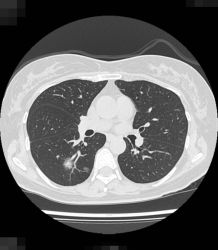

近年増加しているタバコを吸わない女性に多い「肺腺がん」とは、ごく早期のすりガラス陰影といわれるCT検査でしか見えないようながんで、周辺部の影が淡く、直径1.5cm以下であれば、日本肺癌学会のガイドラインでは経過観察でよいとされています。比較的おとなしいがんで、1cm以下のすりガラス状の肺腺がんで女性の場合は、5年後にがんが大きくなっている人は1割程度で、残りの9割の人は大きくならないで、なかには一生そのままの状態の人もいたとの報告もあります。経過観察して、たとえば5年たって大きくなったならその時に、肺を部分的に切除する手術をすればよく、術後の抗がん剤治療も必要ありません。ただ、肺の正常な部分とがん化したすりガラス状に映る影との境界線がはっきりしていたり、影の中にくっきりした部分が広がっている場合は早期ではない可能性があり、注意が必要です。さらに、多発しやすいという性質もあります。

バコを吸わない女性に多い肺がんのCT画像